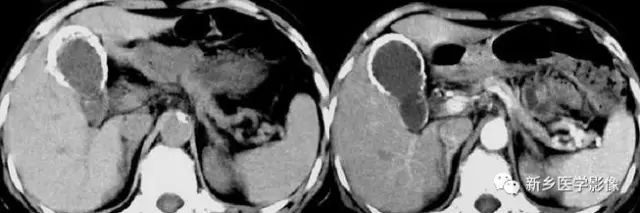

主要包括合并钙化的常见肿瘤或肿瘤样病变,如:肾囊肿,肾细胞癌,多房囊性肾瘤,多囊肝多囊肾囊壁钙化,肾脏结核,肾脏钙乳症